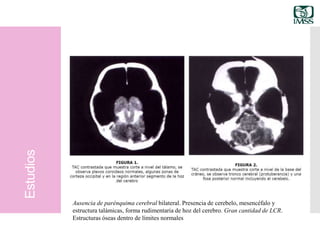

TAC cerebral Ausencia de parénquima cerebral bilateral.

Presencia de cerebelo, mesencéfalo y estructura

talámicas, forma rudimentaria de hoz del cerebro.

Gran cantidad de LCR. Estructuras óseas dentro

de límites normales

Ausencia de parénquima cerebral bilateral. Presencia de cerebelo, mesencéfalo y

estructura talámicas, forma rudimentaria de hoz del cerebro. Gran cantidad de LCR.

Estructuras óseas dentro de límites normales